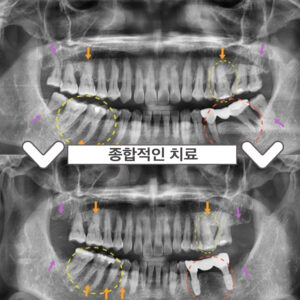

부천서울이로운치과 과거에 치료받았던 보철이 불편하다면? 안녕하세요! 부천서울이로운치과 대표원장 이경중입니다 🙂 앞니는 어금니와 달리 우리가 말할 때나 음식을 먹거나 미소를 지을 때 외부로 드러나 보이는 부분이기 때문에 심미적인 부분에서도 중요한 부분을 차지하게 되는데요. 그렇게 때문에 적절하지 못한 보철물로 인해 보기 좋지 않거나, 잇몸 건강에 문제가 있는 경우 재보철을 통해 더보기…